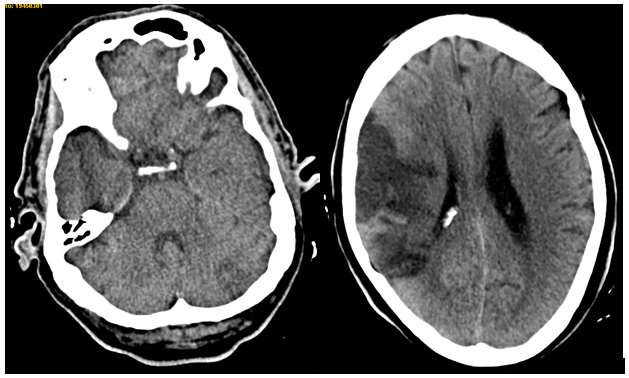

With a diagnosis of brain stroke regarding different vascular regions, the suspected etiology was endocarditis. Blood tests showed increased glomerular sedimentation speed, increased D-dimer (50417) and low platelets (115000). Other complementary exams such as blood serologies, blood and urine cultures were negative. Neurosonological study showed carotid atheromatosis without significant stenosis and a right middle cerebral artery occlusion. In the transthoracic echocardiography a lesion over mitral valvular veil was seen (Figure 2).

Figure 2 Vegetation over mitral vail, showed with transthoracic echocardiography.